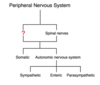

Click on the paravertebral ganglion.

The paravertebral ganglia are where the pre- and postganglionic fibers in the SNS synapse.

There are 31 paired ganglia, and collectively they make up the sympathetic chain.

Click on the white ramus.

In the sympathetic nervous system, the preganglionic sympathetic fibers exit the spinal cord via the ventral nerve roots of the spinal nerves. These fibers enter the sympathetic chain by way of the white communicating rami.